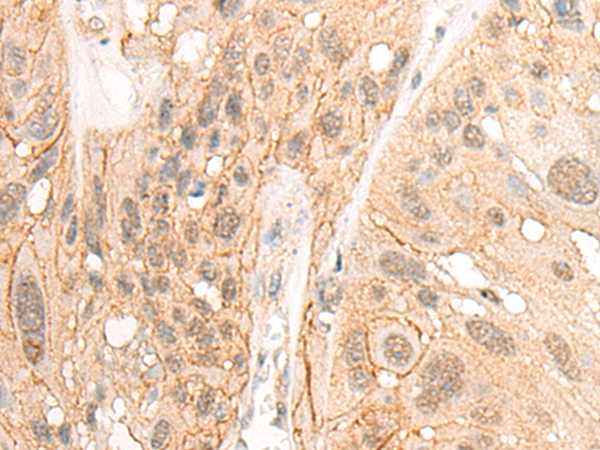

分类: 科研抗体货号: P06307别名: SUR2; CRSP3; MRT18; SUR-2; ARC130; CRSP130; CRSP133; DRIP130应用: IHC反应种属: Human, Mouse, Rat